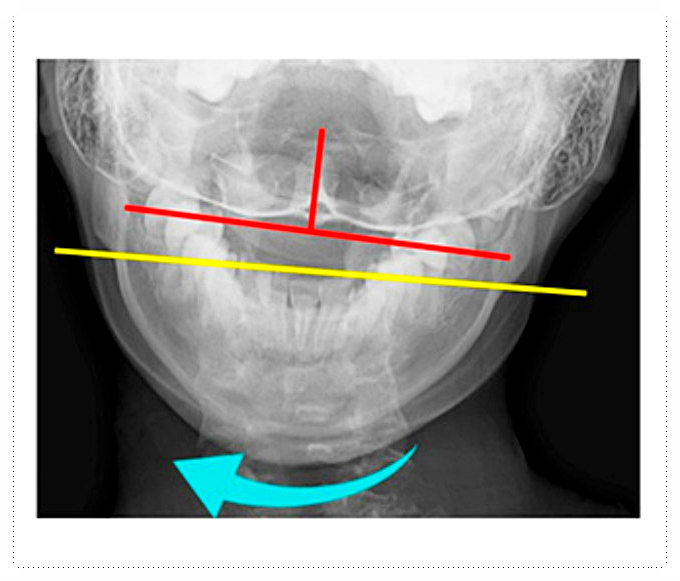

"우리 얼굴의 균형을 결정짓는 진짜 범인? '발바닥'과 '골반'입니다."

많은 사람들이 얼굴 근육만 만지면 안면비대칭이 해결될 것이라고 생각하지만, 사실 우리의 몸은 머리부터 발끝까지 하나로 연결되어 있습니다.

따라서 안면 비대칭 교정을 위해서는 의외로 골반과 발바닥부터 주목해야 합니다.

골반이 틀어지면 그 위에 놓인 척추가 휘어지고, 결국 머리와 목뼈가 어긋나게 됩니다.